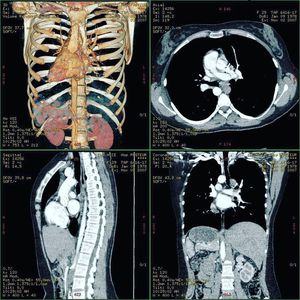

In situs inversus, the organs are reversed/mirrored in their alignment compared to the usual organ composition. This is actually called heterotaxy. Heterotaxy is a rare congenital defect in which the major visceral organs are distributed abnormally within the chest and abdomen. Here you can see that the heart, instead of normally forming on the left side of the chest, is located on the right side. Also the liver is on the left side, causing in the left kidney being placed lower than the right (usually it is the other way round). Heterotaxy has been known to affect the development of the heart, liver, lungs, intestines, and spleen. Babies with Heterotaxy syndrome are usually first identified because they have structural problems with their hearts or livers. For every 1,000,000 babies born, 4 of them will have Heterotaxy syndrome. The exact cause of Heterotaxy is not known, but the symptoms result from the way that the internal organs turn into position during fetal development. This rotation can be affected by many different factors including infection, genetics, or exposures to certain chemicals. There are a few reports of families having several members with Heterotaxy, but the exact cause has not been identified yet.